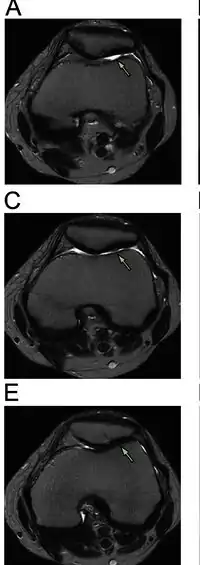

| Diagnostic method | MRI |

- Magnetic Resonance Imaging (MRI) – to observe cartilage condition and assess deterioration